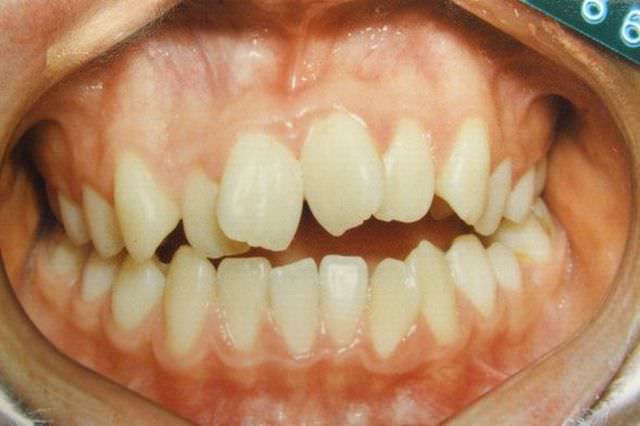

治療前

叢生 治療前

治療後

叢生 治療後

主訴 歯並びが気になる

診断名あるいは主な症状 叢生 乱ぐい歯

年齢 13歳0ヶ月

治療に用いた主な装置 ブラケット装置 スタンダードエッジワイズ法

抜歯部位 非抜歯

治療期間 2年5ヶ月

治療費概算 70万+月々の調整料

リスク副作用 歯の根が吸収して短くなる場合があります。

歯茎が痩せて下がる場合があります。

舌で歯を押す唇を噛む等の癖が改善されない場合は、治療期間が長引く場合があります。

定期的に通院できない、キャンセルが多い場合は治療期間が長引きます。